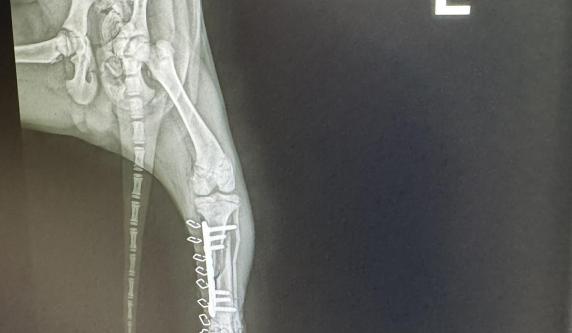

HUBSI 191035000271550 M, 3.1.2026., in the shelter since 18.3.2026., from street near Roma village where he was hit by a car and came with broken back leg. It was operated and he is recoevring very well in Alex's house. X-ray shots are in his album. He is vively, active, playful and happy puppy. He likes attention, and compan yof people and other dogs. At the moment cca 32 cm